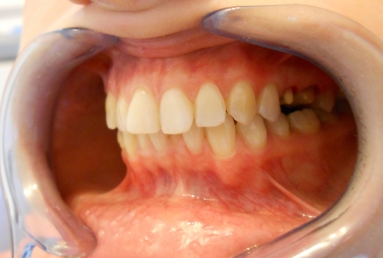

Full ceramic crowns on upper second premolar and first upper molar